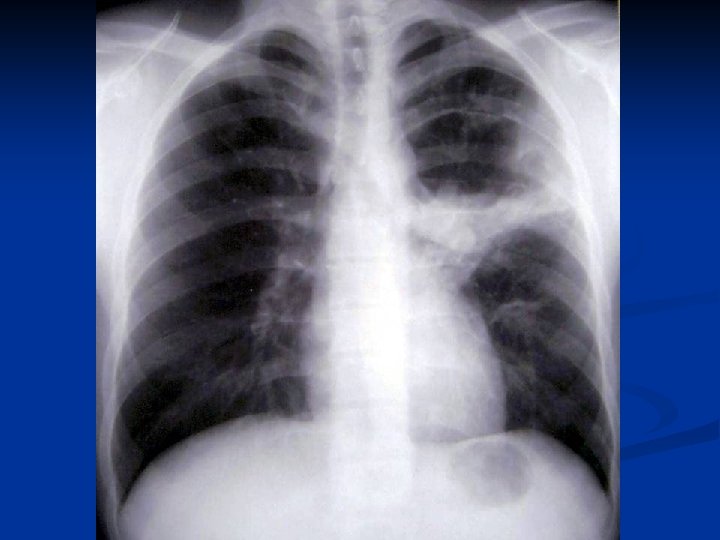

CONSIDERATII GENERALE ASUPRA CHISTULUI HIDATIC PULMONAR C. Mitrofan, A. Aldea, C. Grigorescu, I. Jitaru, C. Moldoveanu, G. Iosep, S. Bolog, M. Radulescu Clinica de Chirurgie Toracica U. M. F. Iasi

Caracteristici generale n n n Boala parazitara determinata de Taenia echinococcus granulosus. Descrisa inca de pe vremea lui Hipocrat si a lui Galen. Termenul de “chist hidatic” utilizat de Rudolphi in 1908. Localizarea pulmonara este a doua ca frecventa dupa cea hepatica. Boala cu distributie endemica in regiunea mediteraneana, Orientul Mijlociu, Australia, Noua Zeelanda, America de Sud.

Material si Metoda n Studiul de fata analizeaza retrospectiv 162 de cazuri operate in perioada 1999 – 2003.

Concluzii n n n CHP evolueaza mult timp asimptomatic sau cu simptome nespecifice. Diagnosticul

Concluzii n n n CHP evolueaza mult timp asimptomatic sau cu simptome nespecifice. Diagnosticul precoce este deosebit de important avand in vedere evolutia acestei boli. Tratamentul medical antiparazitar (Albendazol) este indicat postoperator. Rezectia pulmonara este o metoda de rezerva in tratamentul chirurgical al CHP. Indicatia operatorie este absoluta, tehnica operatorie alegandu-se in functie de caracteristicile fiecarui caz in parte.